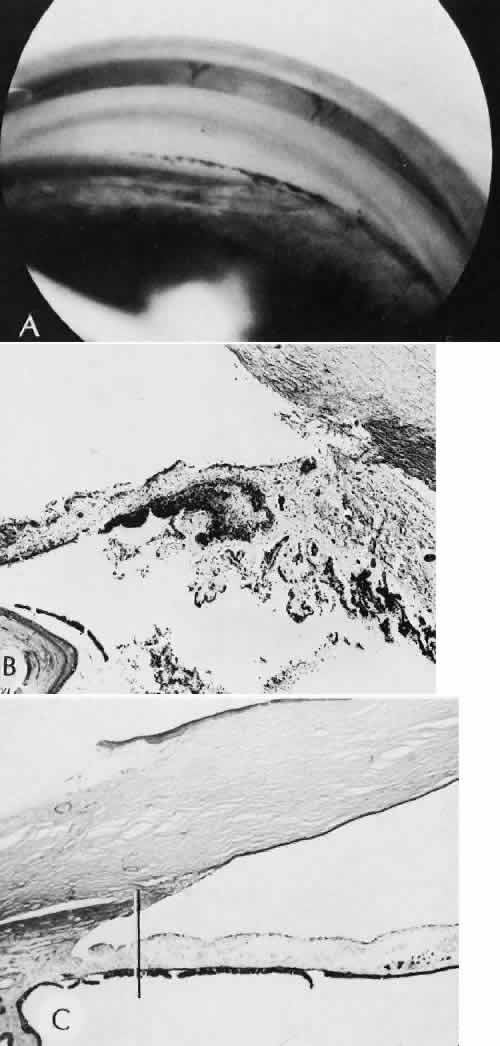

Cyclocryotherapy, cyclodiathermy (Fig. 20), and therapeutic ultrasonography apply energy directly to the pars plicata and cause lysis of the ciliary muscle and occlusion of the vascular supply, leading to extensive necrosis and scarring. Pressure lowering is accomplished by a reduction of aqueous production. Heat applied to the sclera may cause necrosis and localized scleral thinning. Cold applied to the sclera, unless extreme, does not cause any clinical or histologic changes.

Fig. 20. Cyclodiathermy treatment of the ciliary body to control glaucoma. A. Gross photograph illustrates extensive areas of depigmentation mainly in the region of the pars plana (arrows) rather than the pars plicata. B. Light micrograph of the region of the pars plana illustrates an extensive area of tissue degeneration of the pars plana (between arrows) in the late postoperative course. C. Light micrograph of the destructive effects of cyclocryotherapy also in the region of the pars plana and pars plicata. The ciliary epithelium in the early postoperative period is necrotic and cystic. (Hematoxin-eosin stain; A, × 8; B, × 16.)

Cyclodialysis (Fig. 21) creates a cleft between the sclera and the longitudinal muscle of the ciliary body. Aqueous passes directly from the anterior chamber into the suprachoroidal space. Histologically, the longitudinal muscle of the ciliary body is disinserted from the scleral spur. Diaphanous tissue often is present in the suprachoroidal space along the route of filtration. The presence of this tissue differentiates the surgical site from artifactual disinsertion of the ciliary body, which is a common artifact of ocular tissue preparation.

Fig. 21. Light micrograph of cyclodialysis. The region of the surgical cleft between the longitudinal muscle of the ciliary body and the sclera (arrow) is filled with delicate fibrous tissue. Note the posterior location of the anterior face of the ciliary body and the angle recesses in relationship to the scleral spur (S).